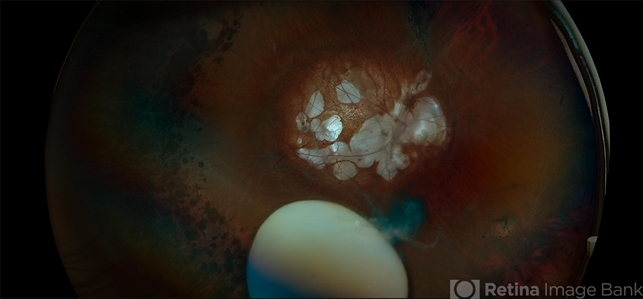

- Subluxation of the Lens, myopic degeneration, lattice degeneration, posterior staphyloma, peripapillary atrophy

- Ultra-wide field fundus photos of an 53-year-old man with a Subluxation of the Lens in the posterior vitreous cavity of the right eye after a trauma that happened many years ago. Patient remains stable with no adverse reaction to the lens at this time. No surgical intervention is recommended at this time. Patient also has myopic degeneration and lattice degeneration that will require patient to have follow up care.